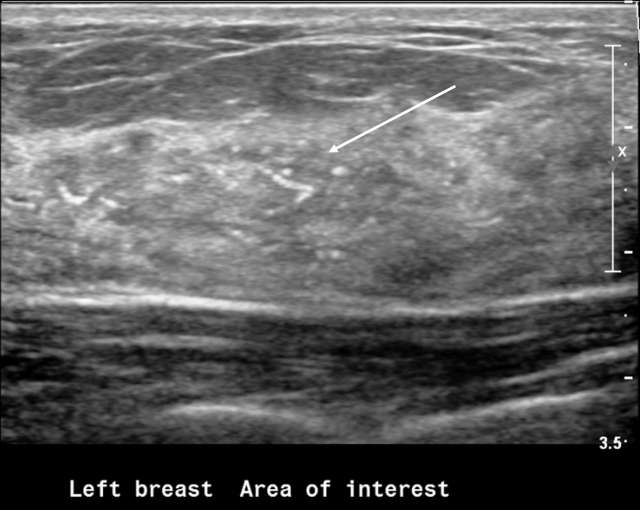

Areas of calcifications without associated abnormal sonographic findings in the surrounding breast tissue

Figure 3. Areas of calcifications (arrow) without associated abnormal sonographic findings in the surrounding breast tissue. The pathology of this area was DCIS.